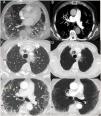

In the preliminary evaluation it was observed an increase in the D-Dimer values (4670μg/L). Computed Tomography Pulmonary Angiography (CTPA) showed a segmental pulmonary thromboembolism (PTE) in LSD and multiple peripheral bilateral ground glass opacities compatible with viral pneumonia. CTPA also showed bilateral varicose bronchiectasis (Fig. 1A and B).

(A) Transverse CTPA images obtained with lung window setting shows multiple pulmonary parenchymal mainly peripheral ground glass opacities (red arrows). Bilateral varicose bronchiectasis (yellow arrows). (B) Maximum intensity projection (MIP) reconstructions images in axial plane shows filling defects (green circle) at the bifurcation level of the anterior segmental branch in right upper lobe compatible with pulmonary thromboembolism. (C–F) Transverse CT images with lung window (C and E) and reformatted Minimum intensity projection (MinIP) reconstructions (D and F) obtained at upper and medium mediastinic levels shows pulmonary interstitial emphysema with air tracking along the right peribronchovascular sheaths ((blue arrows). Central upper anterior right pneumomediastinum (green circles) secondary to a spontaneous barotrauma (Macklin effect). Multiple parenchymal ground glass opacities with prevalent peripheral distribution (red arrows). Bilateral varicose bronchiectasis (yellow arrows).

On day 19 of hospitalization the patient had a worsening of respiratory symptoms it was decided to practice a CTPA to exclude new PTE (D-Dimer 1050μg/L).

We detected a pulmonary interstitial emphysema, with air tracking along the right peribronchovascular with a central anterior right pneumomediastinum, that suggested pneumomediastinum secondary to a spontaneous barotrauma (Macklin effect) in a patient who was not intubated and who has not reported recent chest traumas (Fig. 1B–D, F).